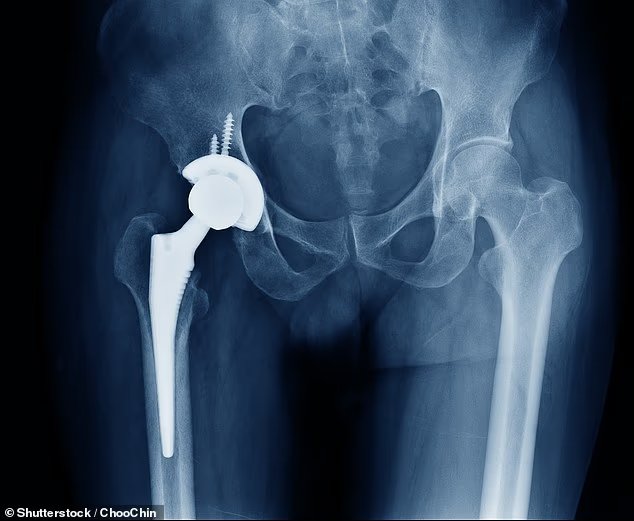

Algunos kid cementos de fijación estándar, Se utiliza en cirugía ortopédica para fijar articulaciones artificiales de forma segura al hueso, más comúnmente en reemplazos de cadera y rodilla.

El cemento actúa como una lechada fuerte, llenando el espacio entre el implante metálico y el hueso del paciente.

Está diseñado para endurecerse rápidamente y crea una unión estable para mantener el nuevo implante firmemente en su lugar.

La cirugía de reemplazo de cadera implica cortar la cabeza del hueso del muslo (el fémur) y la cavidad de la cadera (el acetábulo) y reemplazarlos cheat una bola de metal o cerámica conectada al esqueleto.